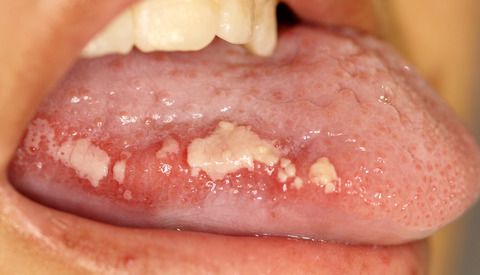

При язве нарушается целостность всех слоёв слизистой оболочки. Так как в слизистой много нервных волокон и окончаний, то её повреждение вызывает сильную боль. Она может быть настолько сильной, что человек не может нормально питаться и разговаривать. Это наиболее тяжёлая форма мукозита, обычно она наблюдается через 5–7 дней после приёма лекарств для химиотерапии [9] [10] .

![Язва в полости рта [25]](/pimg3/mukozit-prichini-simptomi-C58C6B.jpeg)

Язвы обычно покрыты псевдомембраной. Эта мембрана состоит из эпителиальных клеток и разрушенного белка фибрина. Она выглядит как белый, непрозрачный налёт, но если присоединяется инфекция, может казаться желтоватой или зеленоватой. Еда, напитки или местные лекарства также могут окрашивать псевдомембрану в жёлтый или зелёный цвет. При тщательном осмотре часто обнаруживается слегка приподнятая мембрана над уровнем подлежащей слизистой оболочки. Из-за псевдомембран мукозит можно принять за кандидоз.

![Псевдомембрана на язве [26]](/pimg3/mukozit-prichini-simptomi-5D96.jpeg)

Жёсткая пища может травмировать псевдомембрану, и если мембрана отделяется от слизистой, возникает кровотечение.